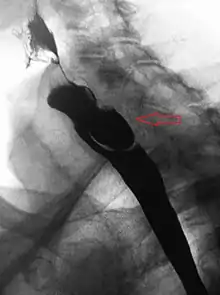

A Zenker's diverticulum, also pharyngeal pouch, is a diverticulum of the mucosa of the human pharynx, just above the cricopharyngeal muscle (i.e. above the upper sphincter of the esophagus). It is a pseudo diverticulum or false diverticulum (only involving the mucosa and submucosa of the esophageal wall, not the adventitia), also known as a pulsion diverticulum.

A combination of the simple barium swallow and a thorough endoscopy will normally confirm the diverticulum.[4]